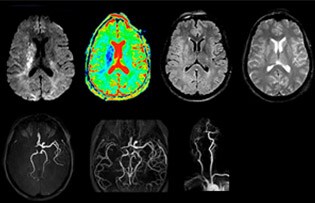

“Ingenia provides great flexibility in the parameters setting. We can tune a sequence the way we want,” says Dr. Savatovsky. “For example, in a stroke exam we use a FLAIR sequence of about two minutes instead of the four-minute FLAIR we use for MS. The diffusion is 30 seconds, the T2*-weighted scan is 30 seconds, the angiography scan time is less than one minute. Ingenia is a great scanner in that situation; even with these fast sequences we can achieve good images with good SNR. When the first sequence tells us that it’s not an ischemic stroke but a hemorrhagic stroke, we may switch to a time-resolved angiography to look for vascular malformations and venous thrombosis.

“Every center is different, but for me the ideal protocol for stroke includes diffusion weighted imaging, FLAIR, and fast susceptibility imaging,” says Dr. Savatovsky. “Our fast susceptibility weighted imaging takes 50 seconds, so it’s as fast as T2*-weighted imaging. It visualizes hemorrhage but also the clots. We also do 3D MR angiography that provides information on cervical and brain vessels. If the patient does not need immediate treatment, or if additional information is needed to decide on treatment, we might also add perfusion imaging and post-contrast T1-weighted imaging.”